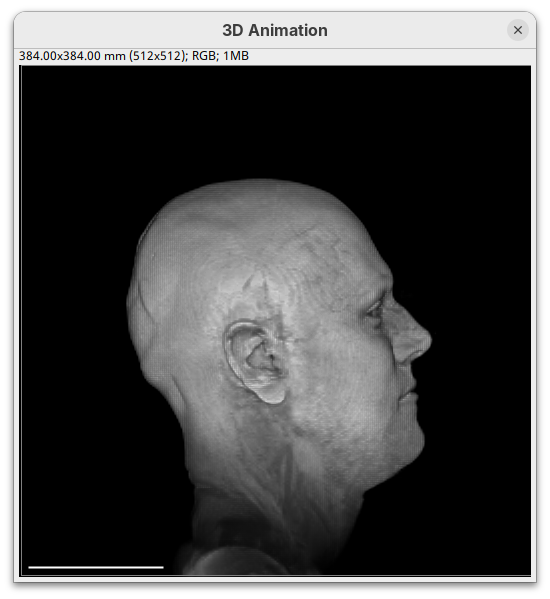

Resetand change theRotation Yto180to look at the right side of the head.

- Now change

Scaleto5andTranslation Xto-500to focus on the nose.